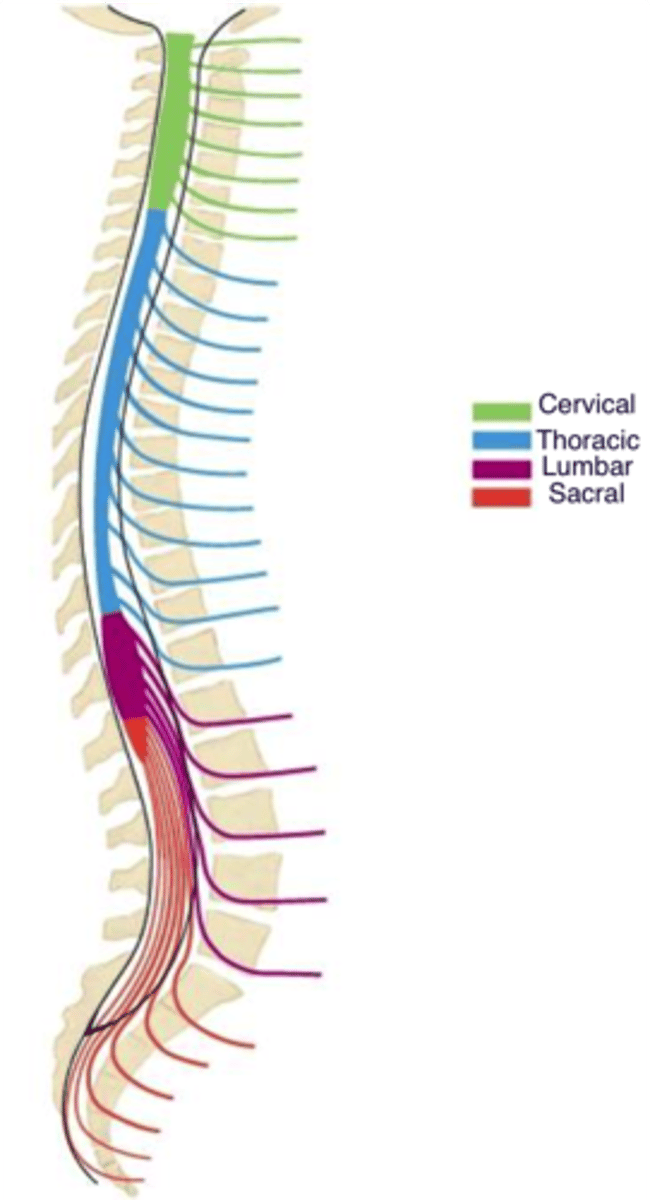

spinal cord structure

Adult length: about 45 cm (18 in)

ends at L1-L2 vertebrae

Segments of the spinal cord

31 segments:

8 cervical

12 thoracic

5 lumbar

5 sacral

1 coccygeal